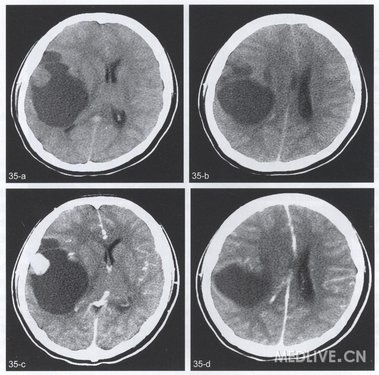

【简要病史】女,23岁。无明昆诱因下间断头痛伴呕吐1个月,呕吐呈喷射状,伴恶心,无抽搐及发热。体检:神志清楚,未引出病理反射。实验室检查未见异常。

【CT与MRI所见】CT平扫(图35a,b)示右侧颞顶叶巨大囊性低密度病灶,CT值19HU,最大径7.0cm,边界清楚,左前外侧壁有两处切迹样改变。外侧囊壁上见一结节状均匀等密度软组织肿块,长径2.Ocm,CT值38HU,该肿块前内侧囊内另见一菲薄分隔样改变。灶周未见低密度带。骨窗显示病变邻近颅骨无破坏、增生及变形。CT增强扫描(图35c,d)上述外侧壁结节显著强化,稍不均匀,CT值达103HU,其余部分囊壁及平扫所见囊内低密度及分隔均无明显强化。病变前内侧可见强化的右侧大脑中动脉及侧裂分支受压内移。

【手术后病理诊断】右额颞叶神经节细胞瘤。

【影像学特点】影像学典型表现为囊性病变与壁结节。CT与MRI均显示肿瘤位于脑表浅部位,较大者占位效应明显,但一般无水肿,病变境界清楚。壁结节紧贴脑膜面,呈CT等或稍高密度、MRI上为稍长T1长T2信号,有时为T2WI低信号,认为其原因是肿瘤细胞核质比较大。囊性部分为CT低密度,MRI长T1、长T2信号,类似脑脊液。增强扫描多不强化,少数强化显著。有些病例可见颅骨变形与吸收。本病可伴脑发育异常,包括巨脑回及脑发育不良等征象。